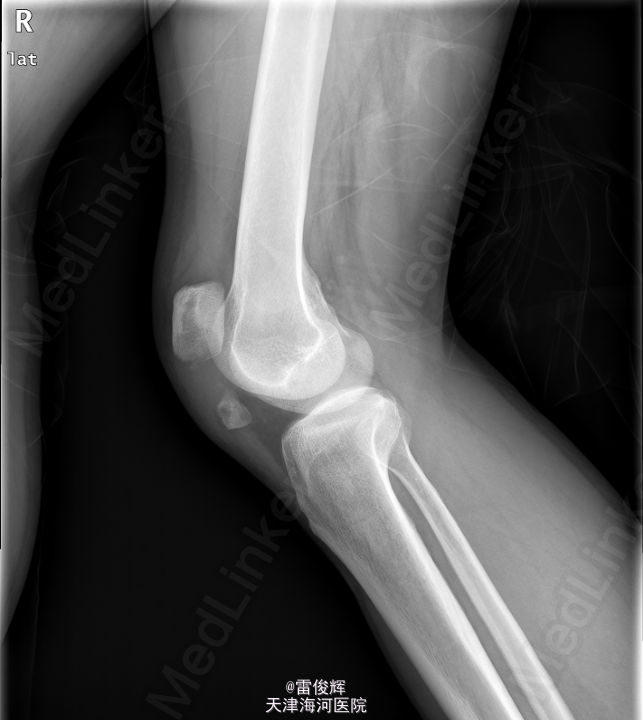

患者,男,46岁,因“外伤致右膝部肿痛伴活动受限3小时”入院。患者于3小时前不右左膝部撞击硬物后感剧烈疼痛,右膝部逐渐肿涨,活动受限,当即不能行走.

右膝关节肿胀明显,皮温不高,皮肤完整无破损,局部散在瘀斑,右膝关节活动受限,关节间隙及髌骨压痛(+),浮髌试验阴性. 本院X线片示:右髌骨骨折。